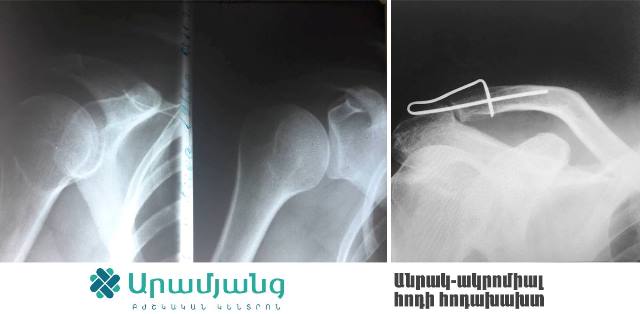

Հիշողություն ունեցող մետաղով բացառիկ վիրահատություններ Արամյանց ԲԿ-ում (ֆոտոշարք)

Արամյանց Բժշկական կենտրոնի փոխտնօրեն, վնասվածքաբան-օրթոպեդ Միքայել Բուռնուչյանի խոսքով՝ սառեցնելով 0-5 աստիճան՝ այս մետաղը հնարավոր է ծալել ու կիրառել ցանկացած դիրքով՝ կախված կոտրվածքի տեղակայումից: Հետո այն մարմնի ջերմության ազդեցությամբ 37-40 աստիճանում կվերադառնա իր նախնական դիրքին՝ ապահովելով ոսկրաբեկորների կոպրեսիան: Մետաղն իր արդյունավետությամբ կարող է փոխարինել նմանատիպ վիրահատությունների ժամանակ կիրառվող մետաղալարին և պտուտակին: Այն իր մեջ պարունակում է ուժ, որն էլ հենց ոսկրաբեկորները պահում է մշտական կոմպրեսիայի վիճակում. արդյունքում ոսկրացման ընթացքն ավելի է արագ է տեղի ունենում: Այն որոշ դեպքում կարելի է կիրառել անգամ Իլիզարովի ծանր ու խոշոր ապարատի փոխարեն՝ազատելով պացիենտին լուրջ անհարմարությունից: Նման փորձ բժիշկ Բուռնուչյանն արդեն կատարել է հինգ ամիս առաջ` նախաբազկի զույգ ոսկրերի կեղծ հոդի վիրահատության ժամանակ օգտագործելով այս մետաղը: Վիրահատությունից հետո պացիենտն իրեն շատ լավ է զգում, իսկ այսօր արդեն կա հստակ արդյունք. մեկ ոսկորը ամբողջովին վերականգնվել է, իսկ մի ոսկորն էլ ամրանալու փուլում է:

Ընդ որում, մետաղը տեղադրելու համար պետք է ընդամենը քիչ ինվազիվ և փոքր միջամտություն կատարել: Մետաղը առաձգական է և ամուր, այն նիկելի և տիտանի խառնուրդ է, ունի տարբեր չափսեր ու ձևեր, որոնք կիրառվում են ըստ դեպքի ու ցուցումի: